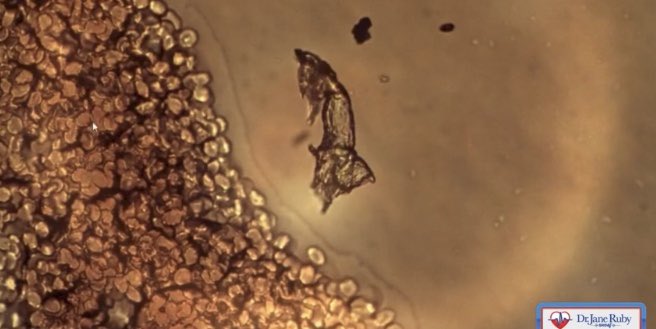

【深刻】接種者の血液異常を調べてきたDr. Phillip「体調不良の未接種者の血液像にも同様の異常を発見」 ▪︎未接種成人(夫人が💉済) ①S蛋白によるダメージで変形したウニ状赤血球 ②黒い輪の中はグラフェンで、似た構造物だけを取り込んで成長する様自己組織化した謎の物体(!) 血液像が夫人と酷似。

▪︎倦怠感などを訴える4-10歳の未接種の子供にも同様の現象が見られる。両親が未接種のケースもあり学校等での伝播の可能性。 ①赤血球の殆どがS蛋白によりダメージを受け団子になり毛細血管を通らない→赤血球の寿命は120日。つまり回復に4ヶ月かかる。 ②子供の血液にもグラフェンや微小血栓。

スパイク蛋白が絡み付いて変形した赤血球が毛細血管を通らず酸素不足や代謝の問題を起こす事は知っていたが、一体この不気味なグラフェンのお化けは何なのか? 「入口と出口がありグラフェンだけを取り込んで成長する有機物質ではない知的物体?」しかも未接種の子供にも⁉︎ rumble.com/v1d1425-dr.-ja…